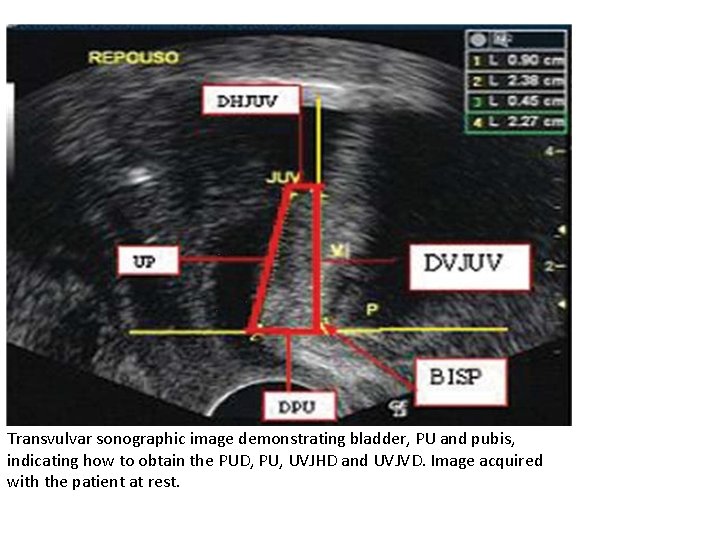

Ultrasonography Vaginal ultrasonography accurately displays descent of the urethrovesical junction, opening of the bladder neck, and detrusor contractions.

Transvulvar sonographic image demonstrating bladder, PU and pubis, indicating how to obtain the PUD, PU, UVJHD and UVJVD. Image acquired with the patient at rest.